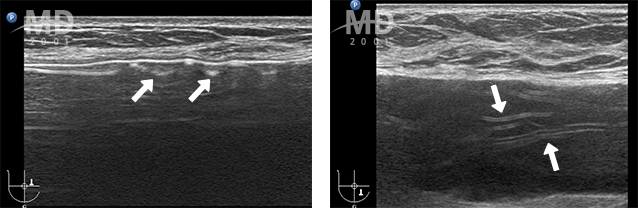

• 수술 후 정상적인 가슴

img

보형물에 맞게 얇고 균일하게 형성된 피막

• 피막에 이상이 생긴 가슴

비정상적으로 두껍게 형성된 피막 매우 두껍고 울퉁불퉁해진 피막